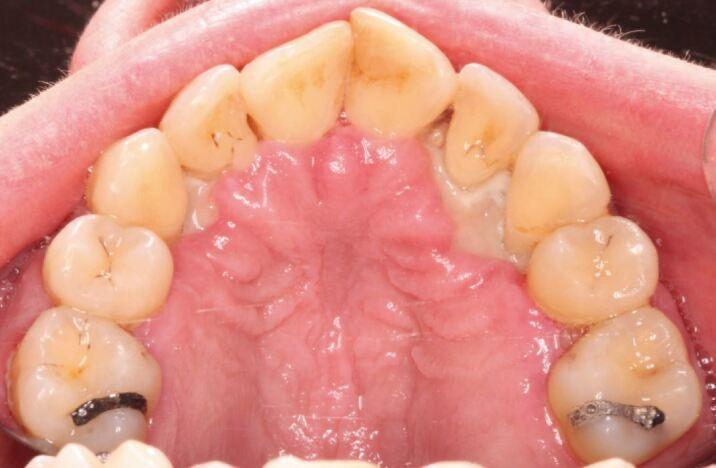

'Necrotising periodontal diseases' is an umbrella term for necrotising gingivitis, necrotising periodontitis, necrotising stomatitis and noma. These rapidly destructive conditions are characterised by pain, interdental ulceration and gingival necrosis which, if left untreated, can result in osteonecrosis. Research indicates that patients with a history of alcohol misuse are at an increased risk of malnutrition, which negatively affects the immune response and predisposition to necrotising periodontal diseases. This article will discuss that osteonecrosis of the alveolar bone does not exclusively occur in association with antiresorptive medications, but can occur as a severe form of necrotising gingivitis. In this article, we will describe two cases to highlight the occurrence, presentation and management of necrotising periodontal diseases secondary to alcohol misuse.

'坏死性牙周病'是坏死性龈炎、坏死性牙周炎、坏死性口炎和口底蜂窝织炎的统称。这些迅速破坏性的疾病的特征是疼痛、牙间溃疡和牙龈坏死,如果不治疗,可能导致骨坏死。研究表明,有酒精滥用史的患者更容易出现营养不良,这会对免疫反应和发生坏死性牙周病的倾向产生负面影响。本文将讨论牙槽骨骨坏死不仅与抗吸收药物有关,还可能作为严重的坏死性龈炎发生。在本文中,我们将描述两例病例,以强调酒精滥用引起的坏死性牙周病的发生、表现和治疗。